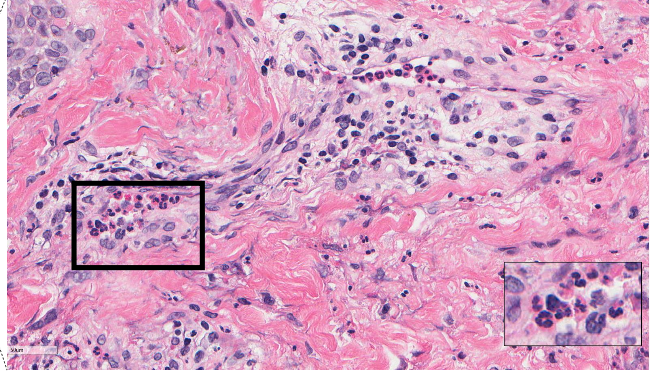

name the biological process shown in this image

chronic inflammation

lymphocytes